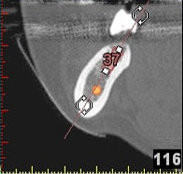

(siehe Bild 3 und 4).

Mit diesen gewonnenen Informationen und Planungen stellt der Zahnarzt interaktiv spezielle Bohrschablonen her. Diese ermöglichen eine exakte Positionierung der Implantate, so wie vorher am Computer geplant.

Weiterhin ist eine auf diese Weise geplante Operation für den Patienten weit weniger belastend. Denn die Freilegung des Knochens ist auf ein Minimum reduziert.